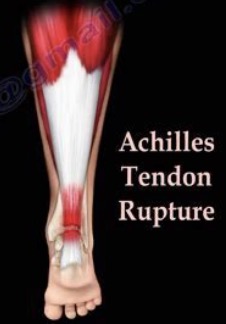

- 布骨医学科普:跟腱断裂修复术后怎么恢复? 布骨康复医疗中心 ,2021-11-25

- 跟腱是人体最强健的肌腱,占小腿跖屈力量的87%,跟腱断裂是一种较常见的运动损伤,75%的跟腱断裂发生于30―40岁男性,通常是在体育运动时出现。一般针对年轻患者或对功能恢复要求较高患者,我们都建议手术治疗。那么术后应该怎么进行恢复呢?.....

- 跟腱断裂术后患者康复指南 布骨康复医疗中心 ,2020-02-24

- 自发性断裂最常发生于30~50岁之间的运动人群,此外,50岁以上的非运动人群及女性也是好发人群。其发生率可达8.3/10万人/年。断裂主要发生在男性。如果有一侧肢体发生过跟腱断裂,发生另一侧跟腱断裂的概率可以增加18倍以上。自发性断裂的原因可能是多方面的,先天性胶原异常、感染性疾病、风湿免疫类疾病、.....